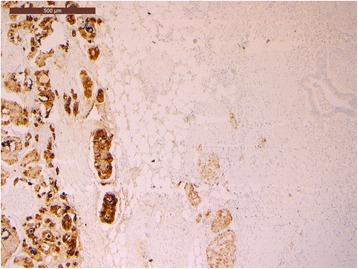

A 69-year-old woman was hospitalized in May 2016 for epigastric pain and weight loss. Her past medical history revealed an undefined main pancreatic duct dilation that was subsequently confirmed at CT scan (23 mm) and endoscopic ultrasound. There was no evidence of pancreatic masses, but the cephalic portion of the main pancreatic duct presented hypoechoic nodules. A diagnosis of the main-duct intraductal papillary mucinous neoplasm was made, and the patient underwent total pancreatectomy. Pathological examination showed a collision tumor constituted by a ductal adenocarcinoma involving the whole pancreas and a neuroendocrine tumor located in the duodenal peripancreatic wall and the head of the pancreas. There was one peripancreatic lymph node metastasis from the ductal adenocarcinoma and eight node metastases from the neuroendocrine tumor. These findings suggested a diagnosis of collision of neuroendocrine and ductal adenocarcinomas of the pancreas. The postoperative course was uneventful.

一名69岁女性于2016年5月因上腹部疼痛和体重减轻入院。她的既往病史显示有未明确的主胰管扩张,随后CT扫描(23毫米)和内镜超声证实了这一情况。没有胰腺肿块的证据,但主胰管头部出现低回声结节。诊断为主胰管内乳头状黏液性肿瘤,患者接受了全胰切除术。病理检查显示为碰撞瘤,由累及整个胰腺的导管腺癌和位于十二指肠胰周壁及胰头的神经内分泌肿瘤组成。导管腺癌有1个胰周淋巴结转移,神经内分泌肿瘤有8个淋巴结转移。这些发现提示胰腺神经内分泌癌与导管腺癌碰撞的诊断。术后过程顺利。